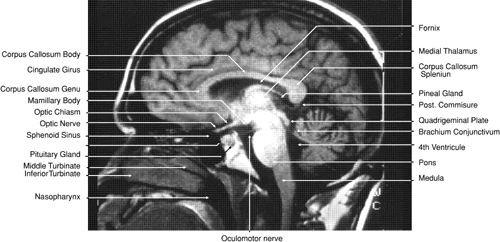

The globe is shown in Figure 12. The orbit and periorbital structures are shown in Figures 13 through 16, and the optic canal is shown in Figures 17 through 26. The cavernous sinus and optic chiasm are shown in Figures 27 and 28, and the posterior visual pathway and cranial nerves are shown in Figures 29 through 33.

Fig. 33. Sagittal T1-weighted image of the brain through the interhemispheric fissure.